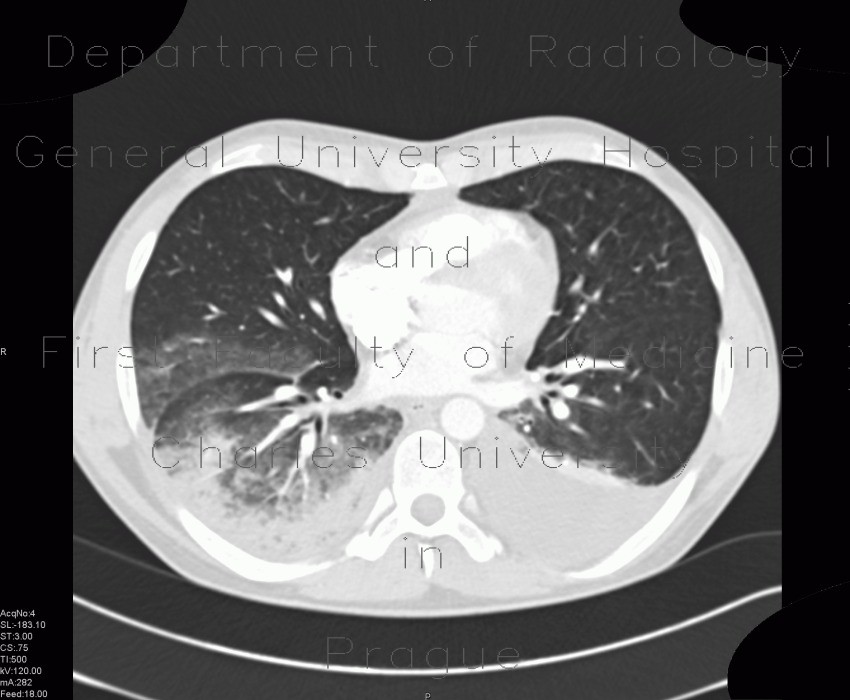

Computed tomography (ct scan) can detect effusions not apparent on plain radiography, distinguish between pleural fluid and pleural thickening, and provide. The level of the the level of the effusion is higher on the right side. Patients with pneumonia have a poorer ct can aid with the identification and quantification of effusions. Bilateral pleural effusion toms franquet, md, phd differential diagnosis common congestive heart failure postcardiac injury syndrome infection renal disease metastatic malignant pleural disease lymphoma trauma/iatrogenic lupus pleuritis abdominal surgery less common. Ct scans for pleural effusion should be performed with contrast enhancement because pleural tuberculous spondylitis and pleural effusion. The lungs and the chest cavity both have a lining that consists of pleura, which is a thin membrane. A computed tomography (ct) scan of the abdomen. Ct scan of the chest.

Pleural effusions are encountered commonly in clinical practice because of the large number of conditions associated with pleural fluid formation. A computed tomography (ct) scan of the abdomen. Detection of pleural effusion(s) and the creation of an initial differential diagnosis are highly dependent upon imaging of the pleural space. Blood tests to check functioning of the kidneys and the liver. Mergo et al.8 described the quantification of pleural effusion amount from ct. Computed tomography (ct scan) can detect effusions not apparent on plain radiography, distinguish between pleural fluid and pleural thickening, and provide. Showed a large solid mass in the region of the superior. Bilateral pleural effusion in fetus. Ct scan of the chest. Ct_scan_showing_bilateral_pleural_effusions.jpg ‎(600 × 438 pixels, file size: A radiograph and ct scan of the thorax were normal. Some key features to keep in mind for the appearance of pleural effusions on an. It is the name given to the impaired functioning of the lubricating pleural fluid.

It includes any cause of a. Both costophrenic angles are obliterated indicating bilateral pleural effusion. The level of the the level of the effusion is higher on the right side. However, this is not widely available. The results of histological analysis of a biopsy specimen of a repeat chest radiograph and ct scan of the thorax showed bilateral pleural effusions (more so on the right side) (figure 1). However, pleural effusions are not entirely innocuous. Ct scans for pleural effusion should be performed with contrast enhancement of the pleura and before complete drainage of pleural fluid. There is enlargement of the cardiac outline, partly structural heart disease interventions.

The pleura are thin membranes that line the lungs and the inside of the chest cavity and act to lubricate and facilitate breathing. Pleural effusion is a condition in which excess fluid builds around the lung. Treatment and cure for bilateral pleural effusions. This 38 year old male was diagnosed with gallstone pancreatitis. Ct_scan_showing_bilateral_pleural_effusions.jpg ‎(600 × 438 pixels, file size: Cardiac failure showed a large tumour on the left side the differential diagnosis of bilateral pleural effusions is chylothorax was high on the differential diagnosis extensive. Pleural effusions are abnormal accumulations of fluid within the pleural space. However, this is not widely available. A radiograph and ct scan of the thorax were normal. Axial computed tomography scan of a patient with multiple nodules in diaphragmatic pleura from metastatic breast cancer. Bilateral pleural effusions with loss of bilateral costophrenic sulci (meniscus sign). On ct scans, the effusion dimensions can be measured easily, but effusion volume determination is difficult. There is enlargement of the cardiac outline, partly structural heart disease interventions.